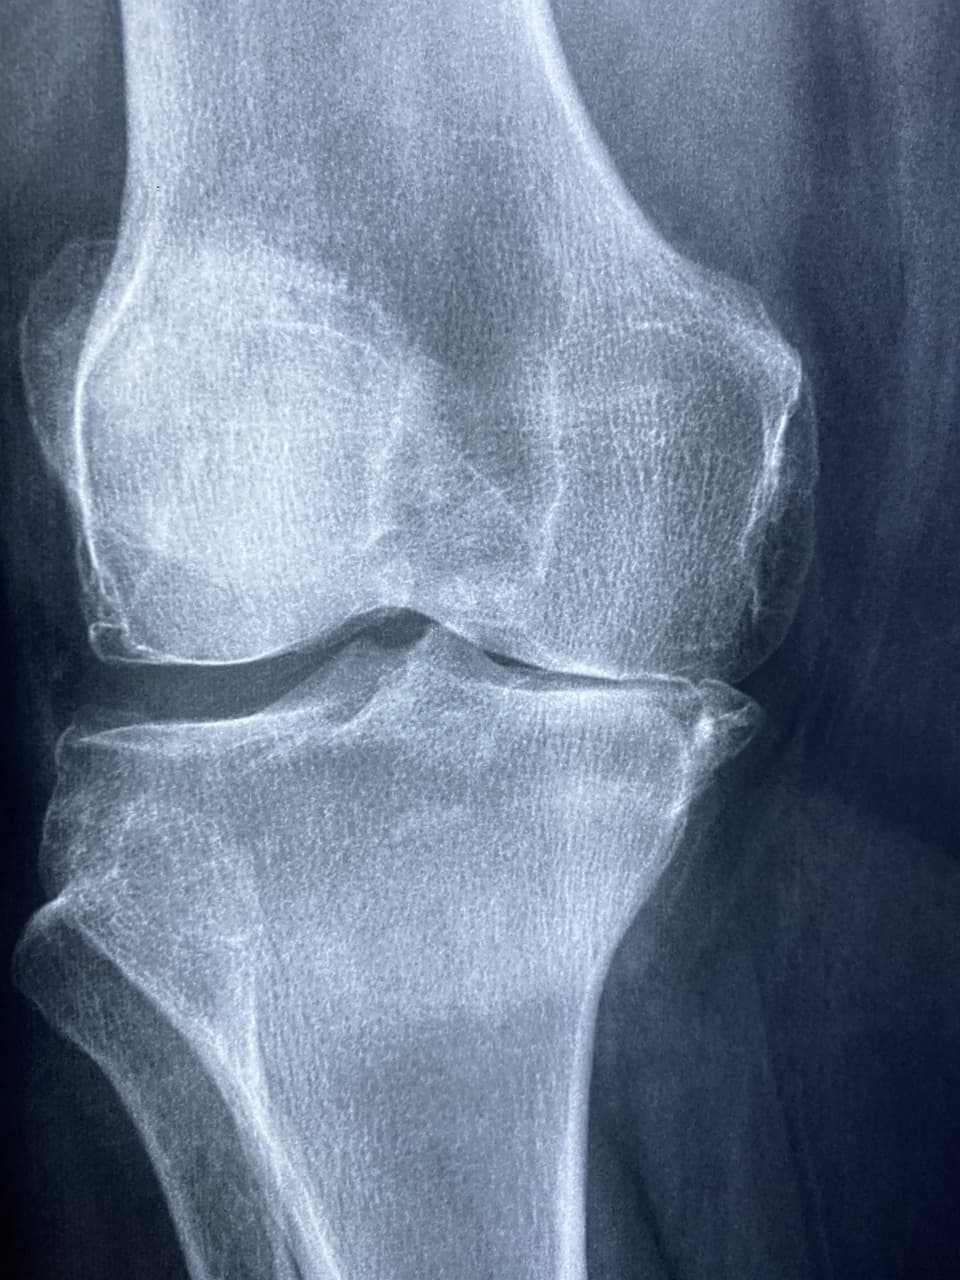

๋ฌด๋ฆŽ์€ ์šฐ๋ฆฌ ๋ชธ์—์„œ ๊ฐ€์žฅ ๋งŽ์ด ์“ฐ๋Š” ๊ด€์ ˆ์ž…๋‹ˆ๋‹ค. ๊ฑท๊ณ , ์•‰๊ณ , ๋›ฐ๊ณ , ๊ณ„๋‹จ์„ ์˜ค๋ฅด๋‚ด๋ฆด ๋•Œ๋งˆ๋‹ค ๋ฌด๋ฆŽ ๊ด€์ ˆ์€ ๊ณ„์† ์›€์ง์ด๋ฉฐ ํ•˜์ค‘์„ ๊ฒฌ๋””์ฃ . ๊ทธ๋ž˜์„œ ๋ฌด๋ฆŽ์€ ์‰ฝ๊ฒŒ ์ง€์น˜๊ณ  ์†์ƒ๋˜๊ธฐ ์‰ฌ์šด ๋ถ€์œ„์ด๊ธฐ๋„ ํ•ฉ๋‹ˆ๋‹ค. ํŠนํžˆ ์ค‘์žฅ๋…„์ธต์ด ๋˜๋ฉด ํ‡ดํ–‰์„ฑ ๊ด€์ ˆ์—ผ์ด๋‚˜ ์—ฐ๊ณจ ๋งˆ๋ชจ๋กœ ์ธํ•ด ํ†ต์ฆ์„ ๋А๋ผ๋Š” ๊ฒฝ์šฐ๊ฐ€ ๋งŽ์Šต๋‹ˆ๋‹ค.